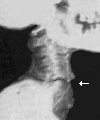

Na Xeroradiografickém snímku bederní páteře Ramsese II. jsou meziobratlové ploténky na člověka s tak vysokým věkem (87 let) příliš vysoké, asi jako u 35 letého muže. Při artróze člověka vysokého věku jsou očekávány vzdálenosti daleko menší. Zlomenina krční páteře je vyznačena šipkou Navíc na rentgenovém snímku krční páteře byla nalezena zlomenina, která byla jednoznačně způsobena až po smrti během mumifikace, při snaze vyrovnat krční páteř. Opravíme-li zlomeninu krční páteře zaujme hlava Ramsese II. známou polohu bechtěrevika.

Na následujícím obrázku je dokreslena pravděpodobná poloha hlavy - napravíme-li zlomeninu páteře. Vidíme, že původní držení hlavy a ostatní zjištění jednoznačně potvrzují diagnózu:

Ramses II. měl Bechtěrevovu chorobu.